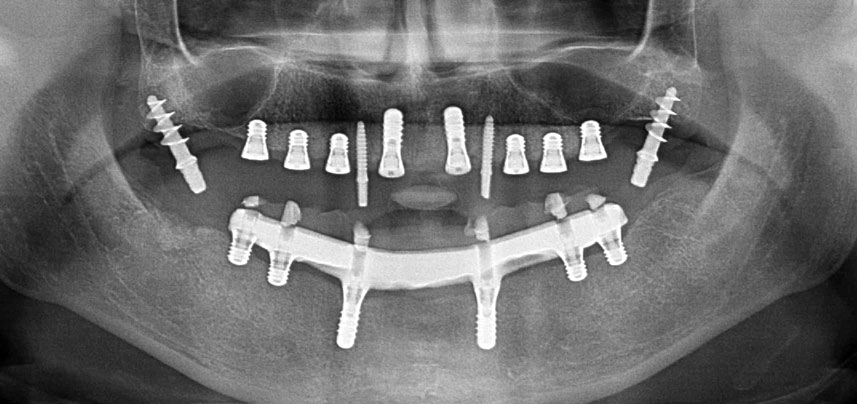

In edentulous patients implant-retained fixed prostheses improve mastication and quality of life. Due to resorption and extensive pneumatization of the sinuses a patient had only a minimal posterior maxillary bone height. The implant sites were prepared with a piezoelectric device and a new set of dedicated instruments. Two 10-mm and six 4-mm implants were placed to retain a bar supported fixed CAD/CAM denture.

Three years later it was time for a maxillary denture of the same type. Based on CBCT planning sinus augmentation was avoided with the aid of short implants, and a surgical template was used to transfer the planned positions to the alveolar ridge (Figs. 1 and 2).

Due to the relatively hard bone (D2) in this area, the 10 mm long implant sites at positions 11 and 21 were finalized with a 4 mm diameter rotary drill, in combination with a W&H WS-75 L surgical contra-angle handpiece, the W&H Implantmed implant motor and the optional W&H Osstell ISQ module. In contrast, due to the soft bone the posterior sites were prepared to a final 3 mm diameter using the Piezomed I3P instrument. The implants were finally placed transgingivally to osseointegrate for three months (Figs. 6-10). The existing denture was retained on four provisional implants (Fig. 8).